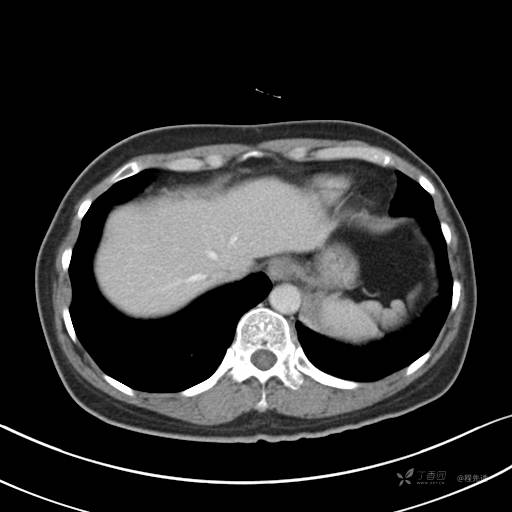

增强动脉期

动脉期CT值约74HU

增强静脉期

静脉期CT值约84HU